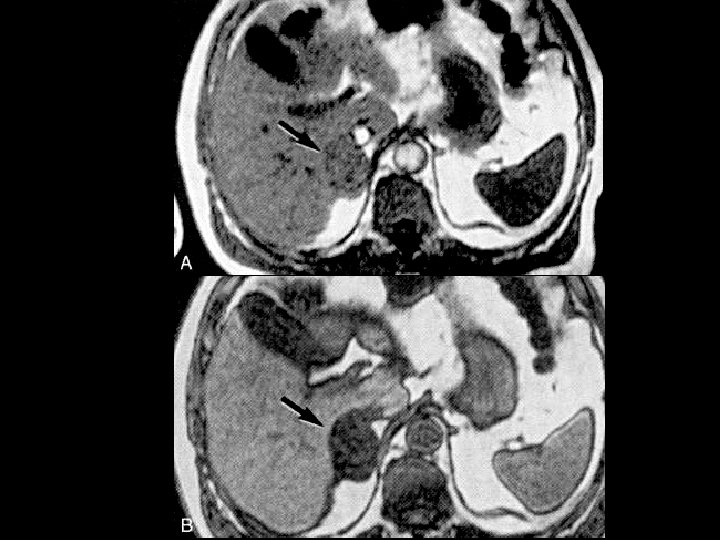

Adrenal adenoma • Findings: – Large right adrenal lesion – Isointense to liver on in -phase scan – Hypointense to liver (signal loss) on out-ofphase scan • ddx: – NONE! – This is an Aunt Minnie!